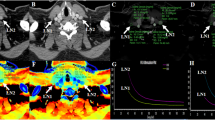

Two hundred and fifty-five LNs (143 non-metastatic and 112 metastatic) were enrolled and allocated to training and validation sets (7:3 ratio). Radiomics features were extracted from arterial and venous phase iodine maps, respectively. Radiomics signature was constructed based on reproducible features using the least absolute shrinkage and selection operator (LASSO) logistic regression algorithm with 10-fold cross-validation. Logistic regression modeling was employed to build models based on CT image features (model 1), radiomics signature (model 2), and the combined (model 3). A nomogram was plotted for the combined model and decision curve analysis was applied for clinical use. Diagnostic performance was assessed and compared. Internal validation was performed on an independent set containing 78 LNs.

Liu X, Ouyang D, Li H et al (2015) Papillary thyroid cancer: dual-energy spectral CT quantitative parameters for preoperative diagnosis of metastasis to the cervical lymph nodes. Radiology 275:167–176

Zhao Y, Li X, Li L et al (2017) Preliminary study on the diagnostic value of single-source dual-energy CT in diagnosing cervical lymph node metastasis of thyroid carcinoma. J Thorac Dis 9:4758–4766

Forghani R, Chatterjee A, Reinhold C et al (2019) Head and neck squamous cell carcinoma: prediction of cervical lymph node metastasis by dual-energy CT texture analysis with machine learning. Eur Radiol 29:6172–6181

Choe J, Lee SM, Do KH et al (2019) Prognostic value of radiomic analysis of iodine overlay maps from dual-energy computed tomography in patients with resectable lung cancer. Eur Radiol 29:915–923